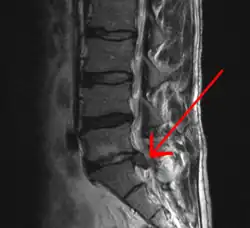

A herniated disc as seen on MRI, one possible cause of low back pain

An intervertebral disc has a gelatinous core surrounded by a fibrous ring.[35] When in its normal, uninjured state, most of the disc is not served by either the circulatory or nervous systems – blood and nerves only run to the outside of the disc.[35] Specialized cells that can survive without direct blood supply are in the inside of the disc.[35] Over time, the discs lose flexibility and the ability to absorb physical forces.[26] This decreased ability to handle physical forces increases stresses on other parts of the spine, causing the ligaments of the spine to thicken and bony growths to develop on the vertebrae.[26] As a result, there is less space through which the spinal cord and nerve roots may pass.[26] When a disc degenerates as a result of injury or disease, the makeup of a disc changes: blood vessels and nerves may grow into its interior and/or herniated disc material can push directly on a nerve root.[35] Any of these changes may result in back pain.[35]